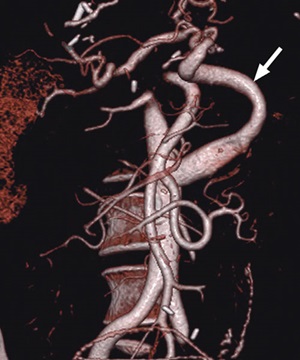

Aortohepatic conduit in a 52-year-old woman 1 year after a second liver transplant. Cinematic rendering of CT angiography shows an aortohepatic conduit (arrow), which is an alternative surgical technique for creating an arterial anastomosis. An aortohepatic jump graft was placed by using a donor iliac vein.